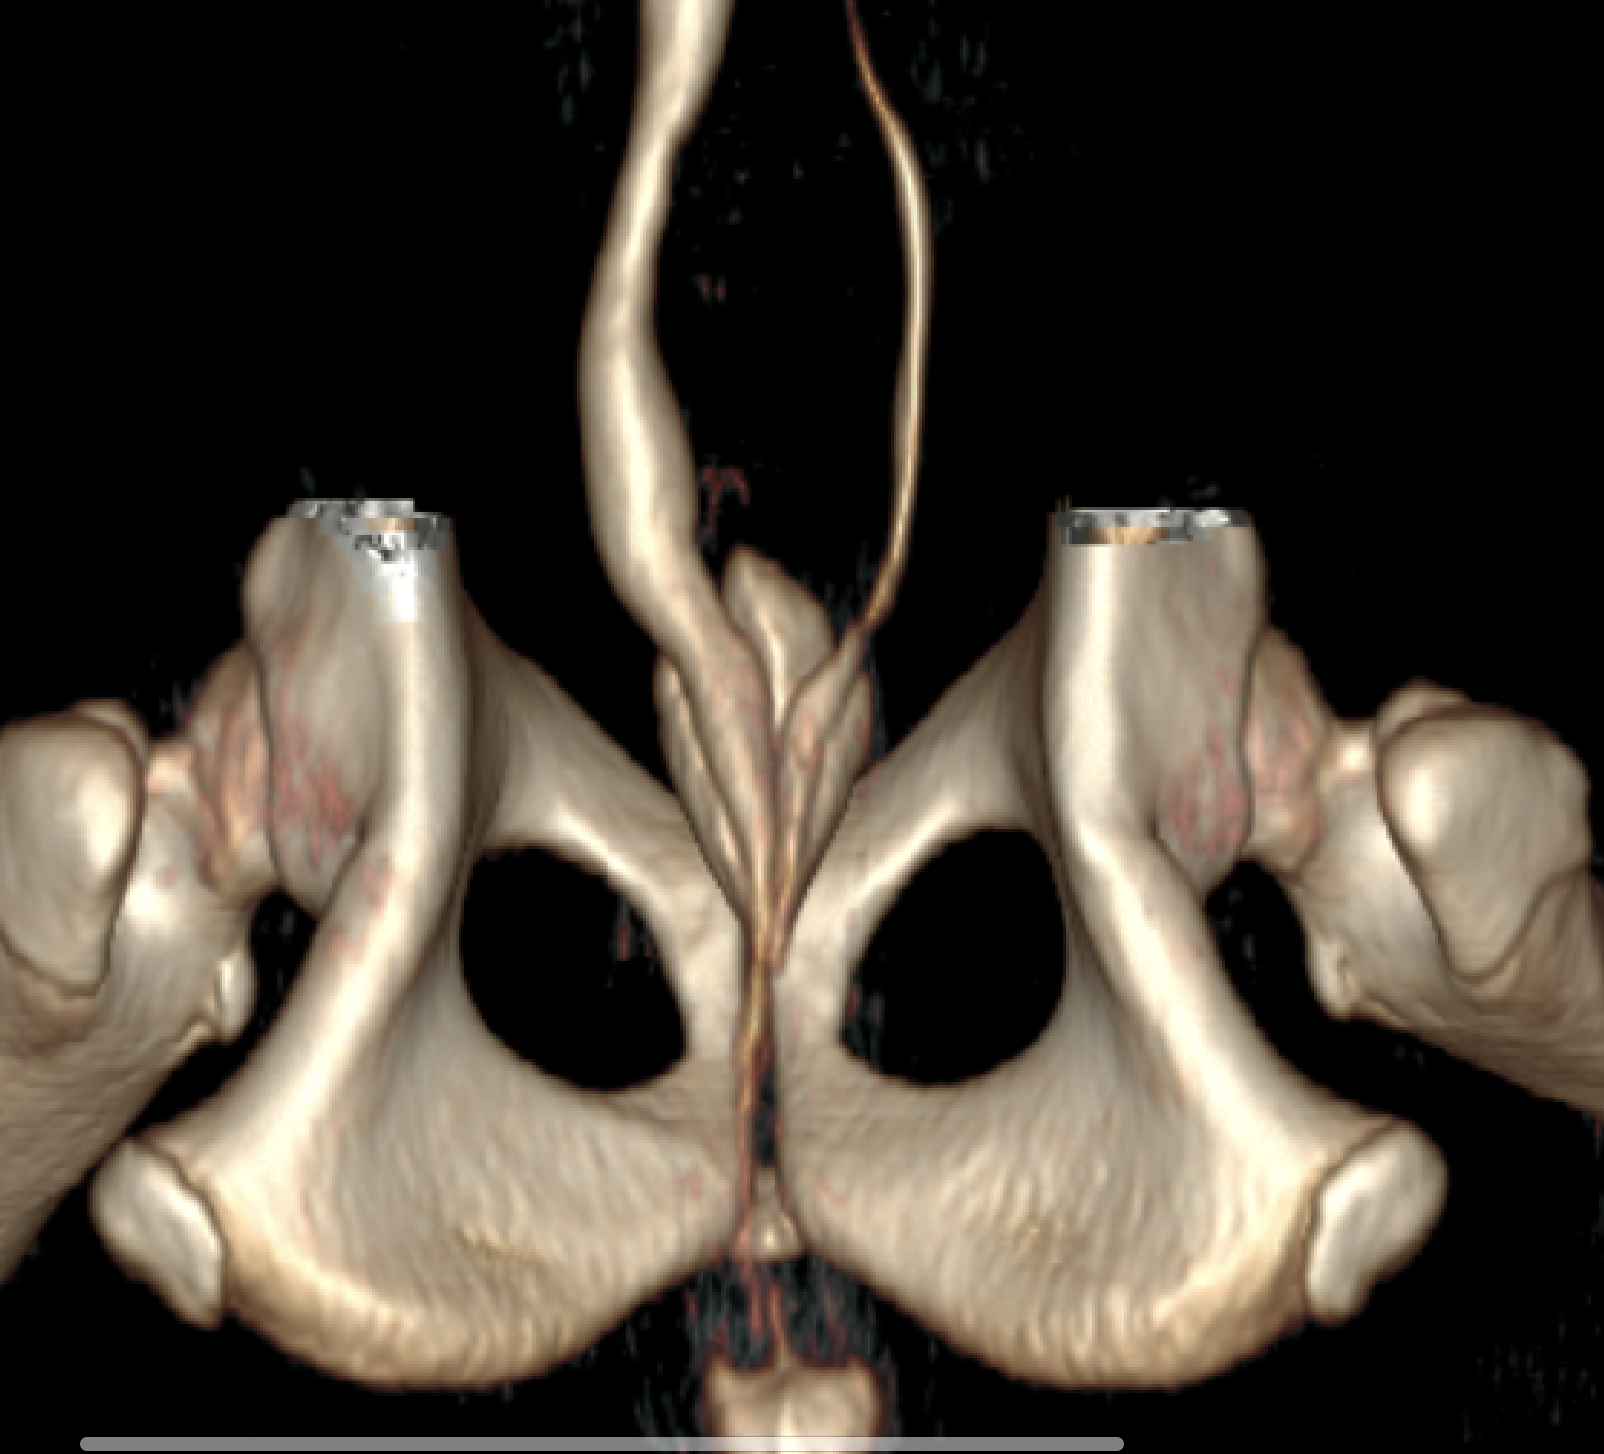

骨盤骨折

猫ちゃんで交通事故により骨盤骨折を生じていた症例です。 レントゲン検査では腸骨、寛骨臼の骨折が確認されたがCT検査では寛骨臼を含む頭側領域での粉砕骨折であった。左右恥骨の骨折も確認された。 仙腸関節脱臼はなし。 2日ほど他院で状態改善のための入院を実施しており、正常な排尿も確認されていた。 手術内容としては、 骨片同士を配列することは困難と判断し架橋プレートとした。また寛骨臼が厳密に整復出来ないことを考慮し、大腿骨頭骨頸部切除も実施した。大転子骨切り術にて臀筋を脱転させ、プレートを設置した。続いて大腿骨頭骨頸部切除を実施。恥骨の骨折断端部が骨盤腔側に迫り出さないように腸骨にワイヤリングした。その後、テンションバンドワイヤーにて大転子を整復し、閉創した。